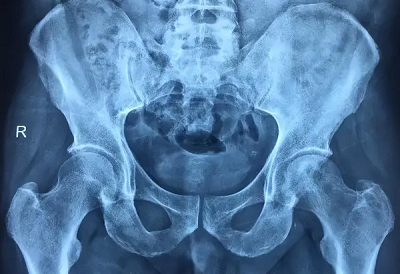

之前我在长达七年的求医治疗过程中依旧是行走困难、疼痛难忍,饱受疾病之痛苦,已经身心俱疲,从去年3月份腿部疼痛加重,左边臀部酸痛无力而且拉扯着痛,左边腿长短腿严重,平躺时无力抬起,右边股骨头尤其疼痛,还因为疼痛牵拉代偿使骨盆旋转导致驼背严重。

看诊时,郝召霞主任非常详细的了解了我的情况,并根据我的症状,为我制定了通血生骨方内服外用相结合的治疗方案,在郝主任的详细讲解下,我了解到治疗的根本目的是要针对坏死病根,把局部瘀堵血脉打通,让股骨头恢复正常供血,这样骨质才能逐渐提升恢复,病症才能有效减轻或消除,后期保护好病情才不容易再有反复。

在郝主任的精心治疗下,我的股骨头血运恢复、新骨再生方面都有显著成效,疼痛症状已经完全消失,腿能正常用力了,走路也很轻松,我心情也变好了,别人都说我变得开朗了。真的非凡感谢郝主任。